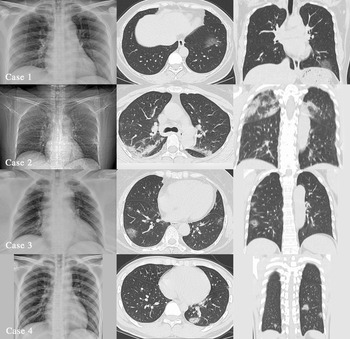

From January to February 2020, 4 patients with common COVID-19 were admitted and treated, and all 4 patients had a similar history from the Wuhan epidemic area and contact with patients confirmed with the disease. Three were female and 1 was male; 3 were young adults and 1 elderly. All 4 patients had fever not higher than 38.5°C. There were 2 cases of pharyngeal discomfort, 2 cases of dry cough, 1 case of productive cough, 1 case of muscle pain, 2 cases of headache, and 2 cases of fatigue (Table 1). None of the 4 patients showed nasal congestion, runny nose, vomiting, diarrhea, chest tightness, or shortness of breath. Chest examinations showed no positive signs, such as rhonchi or moist crackles, in both lungs. Peripheral blood leukocyte and lymphocyte decreased significantly in only 1 case. A pharyngeal swab SARS-CoV-2 ribonucleic acid (RNA) test was performed in 1 patient that was initially negative, 1 patient with twice negative, and 2 patients with initial positive. As for SARS-CoV-2 RNA pharyngeal swab test results, 1 was initial negative, 1 was twice negative, and 2 were initial positive (Table 2). Chest X-ray examinations were negative in all patients. Chest computed tomography (CT) scans showed multiple plaque, interstitial changes, and ground glass opacity in all 4 patients; a small amount of bilateral pleural effusion was observed in 1 patient (Figure 1; see Table 2).

FIGURE 1 Four Patients’ Imaging Findings.

Patients’ imaging results included the following:

Case 1: X-ray negative; CT: ground glass opacity of inferior lobe of left lung.

Case 2: X-ray negative; CT: multiple patchy ground glass opacity in both lungs with a small amount of effusion on both lungs.

Case 3: X-ray negative; CT: multiple patchy ground glass opacity on both lungs.

Case 4: X-ray negative; CT: multiple patchy ground glass opacity on both lungs.

A prominent feature of the 4 patients was that the clinical signs and symptoms were inconsistent with the imaging: Signs and symptoms were mild, including normal pulse oxygen saturation, whereas the CT images showed that patients’ conditions were severe. According to the clinical signs and symptoms, all 4 cases were common mild cases, but the chest CT showed viral pneumonia, such as different levels of multiple patchy ground glass opacity and interstitial changes, and even 1 case had bilateral pleural effusion. However, all patients underwent a chest X-ray examination before a CT examination, and no positive results were found. Therefore, for suspected patients, 7 especially those with no evidence of etiology, we cannot always evaluate the lung condition comprehensively and objectively through a chest X-ray examination, so that misdiagnosis happens and affects treatment. Therefore, an early chest CT examination is relatively reliable, which may reduce the rate of a missed diagnosis. The value of quantitative analysis of chest CT images for the diagnosis of this disease needs to include more cases for further research.